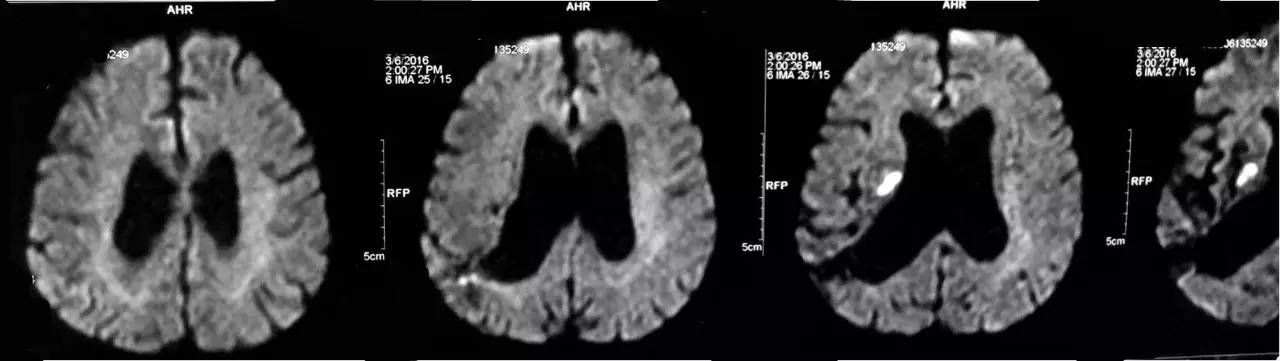

患者目前应用阿司匹林100mg/d,硫酸氢氯吡格雷75mg/d,阿托伐他汀钙片20mg/d治疗,系统内科治疗后患者双下肢行走不稳症状较前明显改善。但患者近三日出院发热,考虑肺部感染给予抗生素治疗,于2016-3-16 15:30出现言语不能及进食呛咳。MRI检查提示:双侧基底节、放射冠急性/亚急性腔隙性脑梗死。患者出现新鲜梗死,请帮助分析梗死原因,及下一步诊治方案。

▼头DWI(2016-3-6)